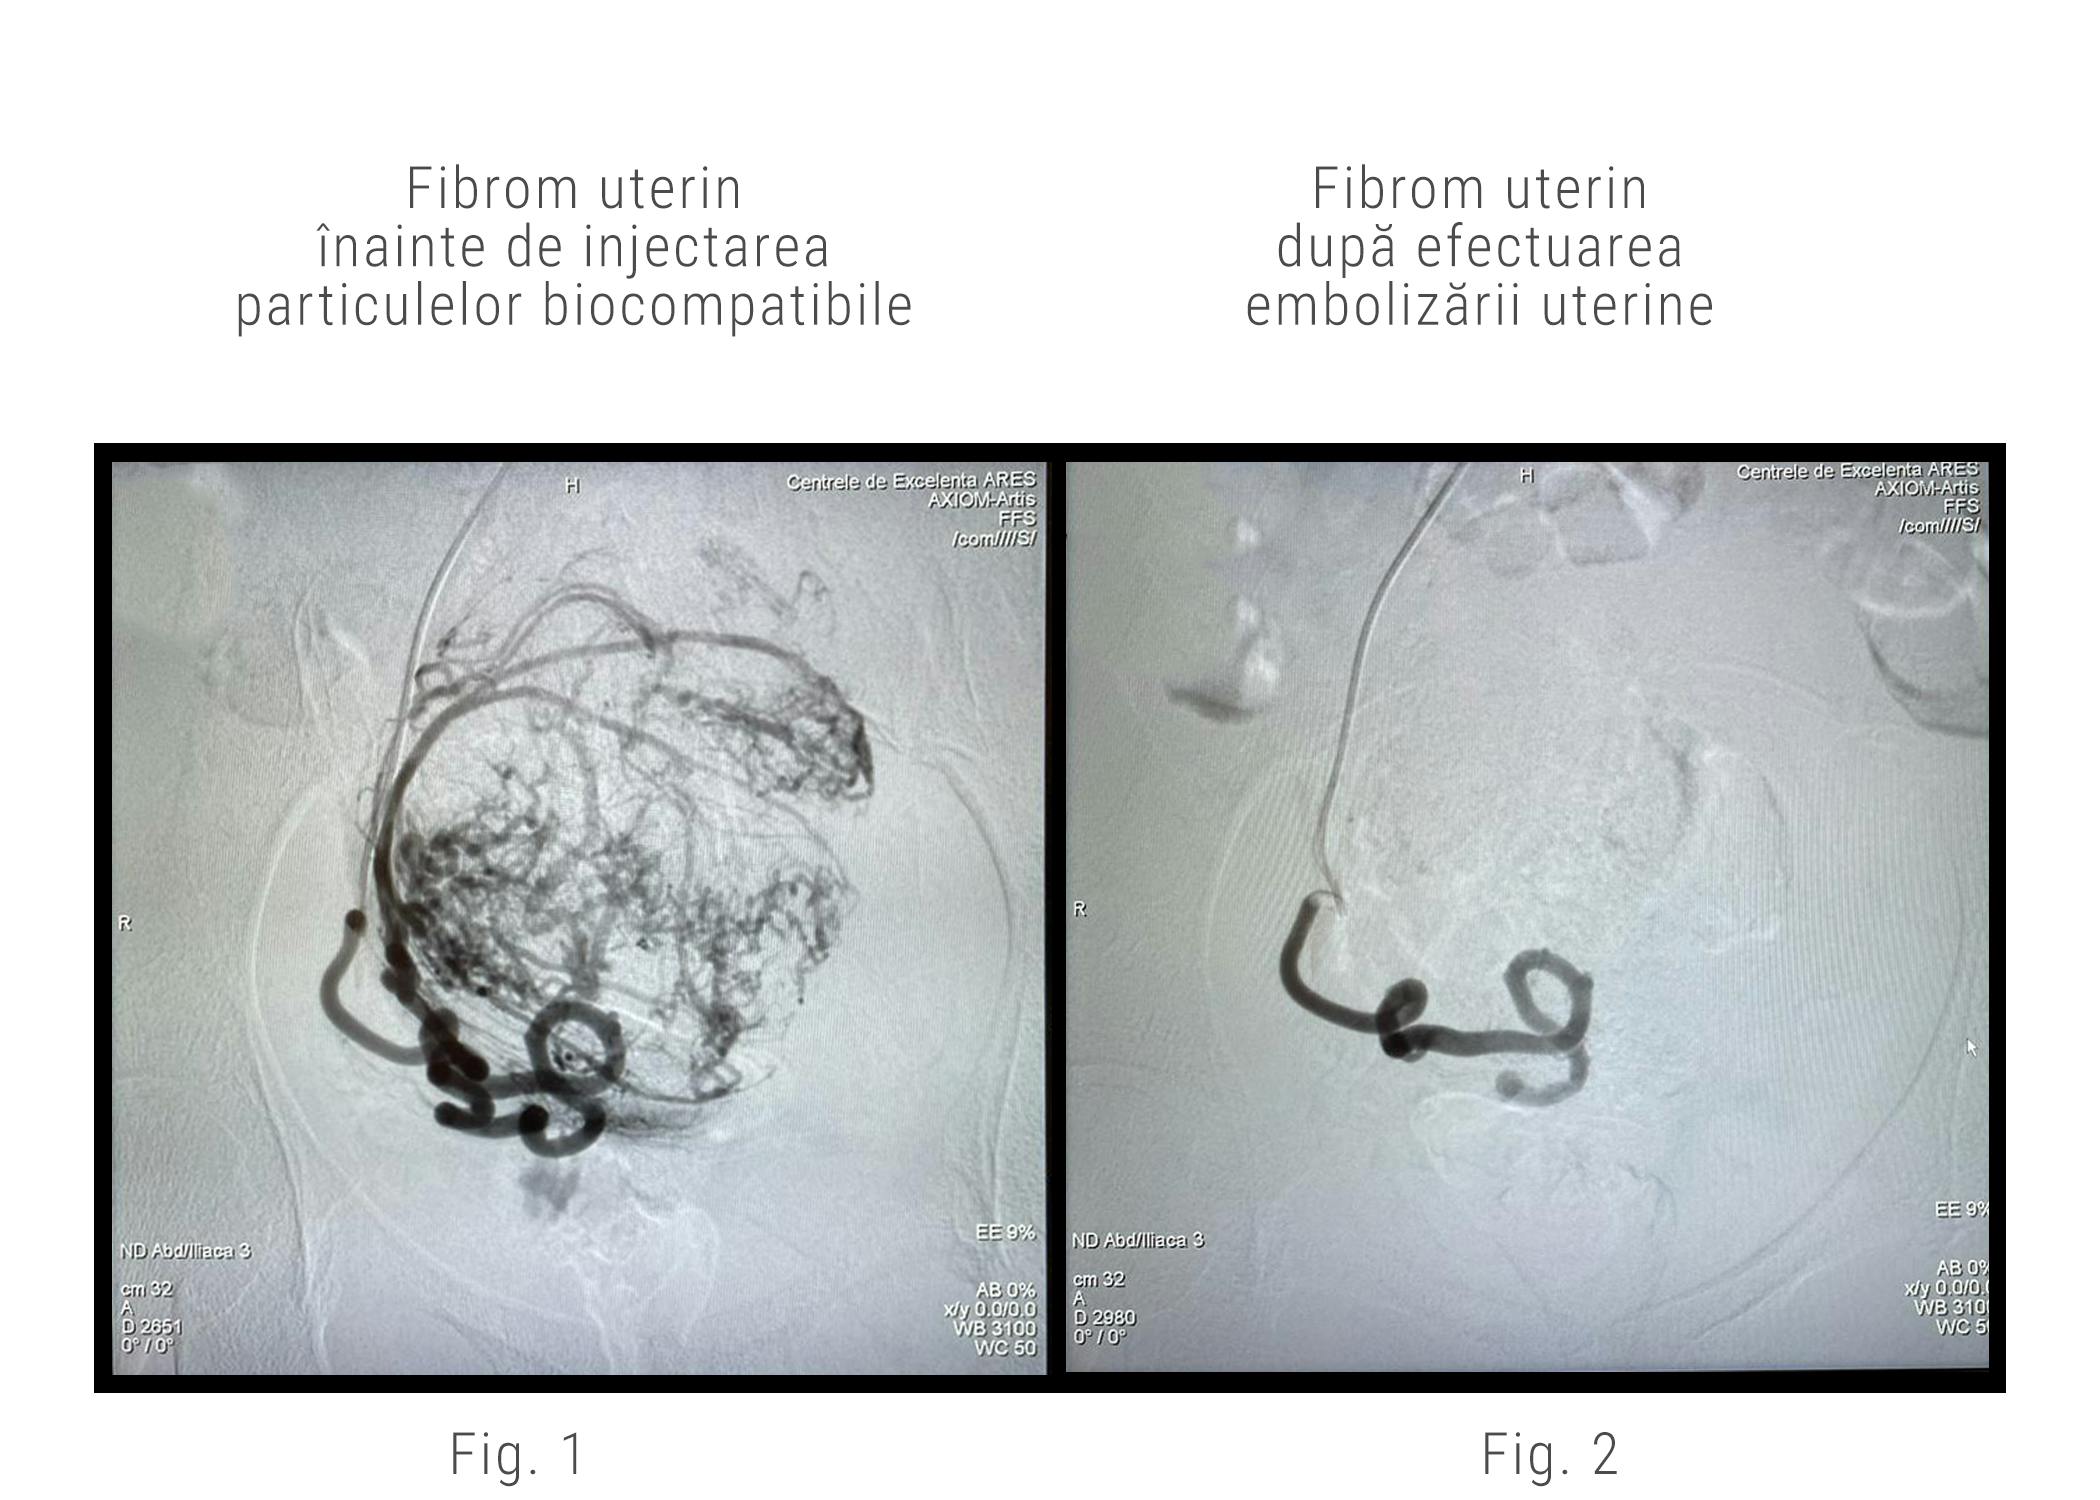

Dr. Rareș Nechifor a ghidat cateterul până la nivelul arterelor uterine folosindu-se de imaginile de pe monitoarele aparatului de angiografie. Odată ce a ajuns la acest nivel, a injectat substanță de contrast pentru a vizualiza arterele care alimentează fibromul uterin.

Următorul pas după identificarea arterelor care hrănesc fibromul este acela de a le astupa prin injectarea unor micro-particule biocompatibile. Astfel se întrerupe alimentarea cu sânge a fibroamelor și se va obține o devascularizare completă. Mai simplu spus, fibromul uterin nu va mai primi sânge, va intra într-un proces de resorbție și își va micșora volumul.

După astuparea arterelor uterine care alimentau fibromul, dr. Rareș Nechifor a efectuat o scopie de control pentru a se asigura că fibromul nu mai primește sânge. După acest control, a retras instrumentele medicale, iar la locul de puncție, asistenta medicală a efectuat un pansament compresiv.